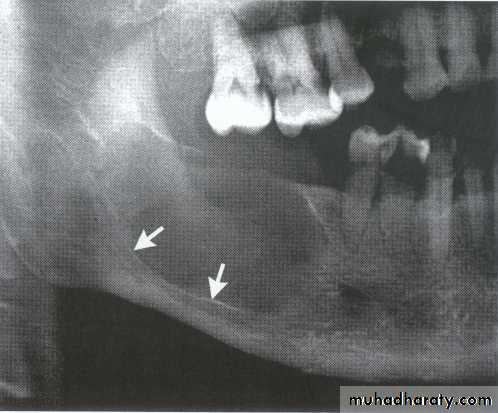

Histiocytosis-X (Langerhans cell disease):They are three manifestations produce tumour-like lesions in bone, caused by proliferation of Langerhans cells and eosinophilic leucocytes.

Radiographically :

• Multiple radiolucent areas in the interdental & interradicular bone.

• teeth seem to hang in air. Exfoliation of teeth & teeth germ are common, ulceration of overlaying mucosa.

• Multiple radiolucent foci seen in the skull & long bone of the skeleton, lesion in the skull give appearance of geographic map , with skull enlargement .

• Histiocytosis-X

• Eosinophilic Granuloma (2nd-3rd decade of life).• Hand-Schüller-Christian disease (1stdecade of life).

• Letterer-Siwe disease (before 2 years of age).